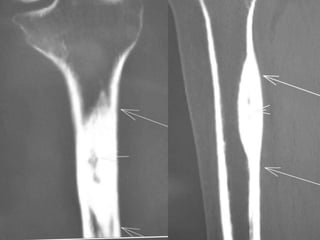

• The tumor may be found in cortical or

cancellous bone, producing a distinct x-ray

appearance of cortical sclerosis.

Osteoid Osteoma

• CT may detect the nidus, whereas

roentgenograms show only sclerosis.

Osteoid Osteoma - CT

• CT is more accurate than MRI.

• CT helped in confirming the diagnosis of

osteoid osteoma in 74% of cases.

• Szendroi et al reported accuracies of about

66% in the diagnosis of intra-articular lesions

and 90% in extra-articular lesions.

• To date, CT scanning is the primary

investigational tool for the definitive diagnosis

of osteoid osteoma.